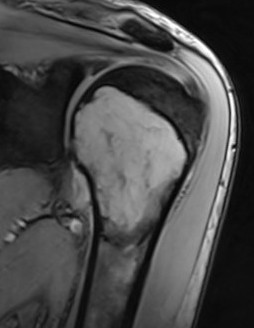

MRI

Low signal intensity T1 / high signal intensity T2

Areas of ABC seen in 10 - 14%

Look for signs of grade III: soft tissue extension